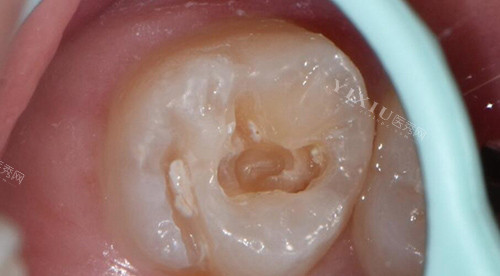

诊室门开了,叫到我的名字。推开门,白大褂医生站起来伸手:“我是张医生,先别紧张,咱们慢慢来。”他先让我躺到牙椅上,调暗灯光,用小镜子仔细扒拉我的牙齿:“左下6号牙有个龋洞,已经到牙神经了,得做根管治疗。”说着调出电脑里的牙片——原来那个小黑点底下,牙神经已经被腐蚀得只剩一点,怪不得疼得这么凶。